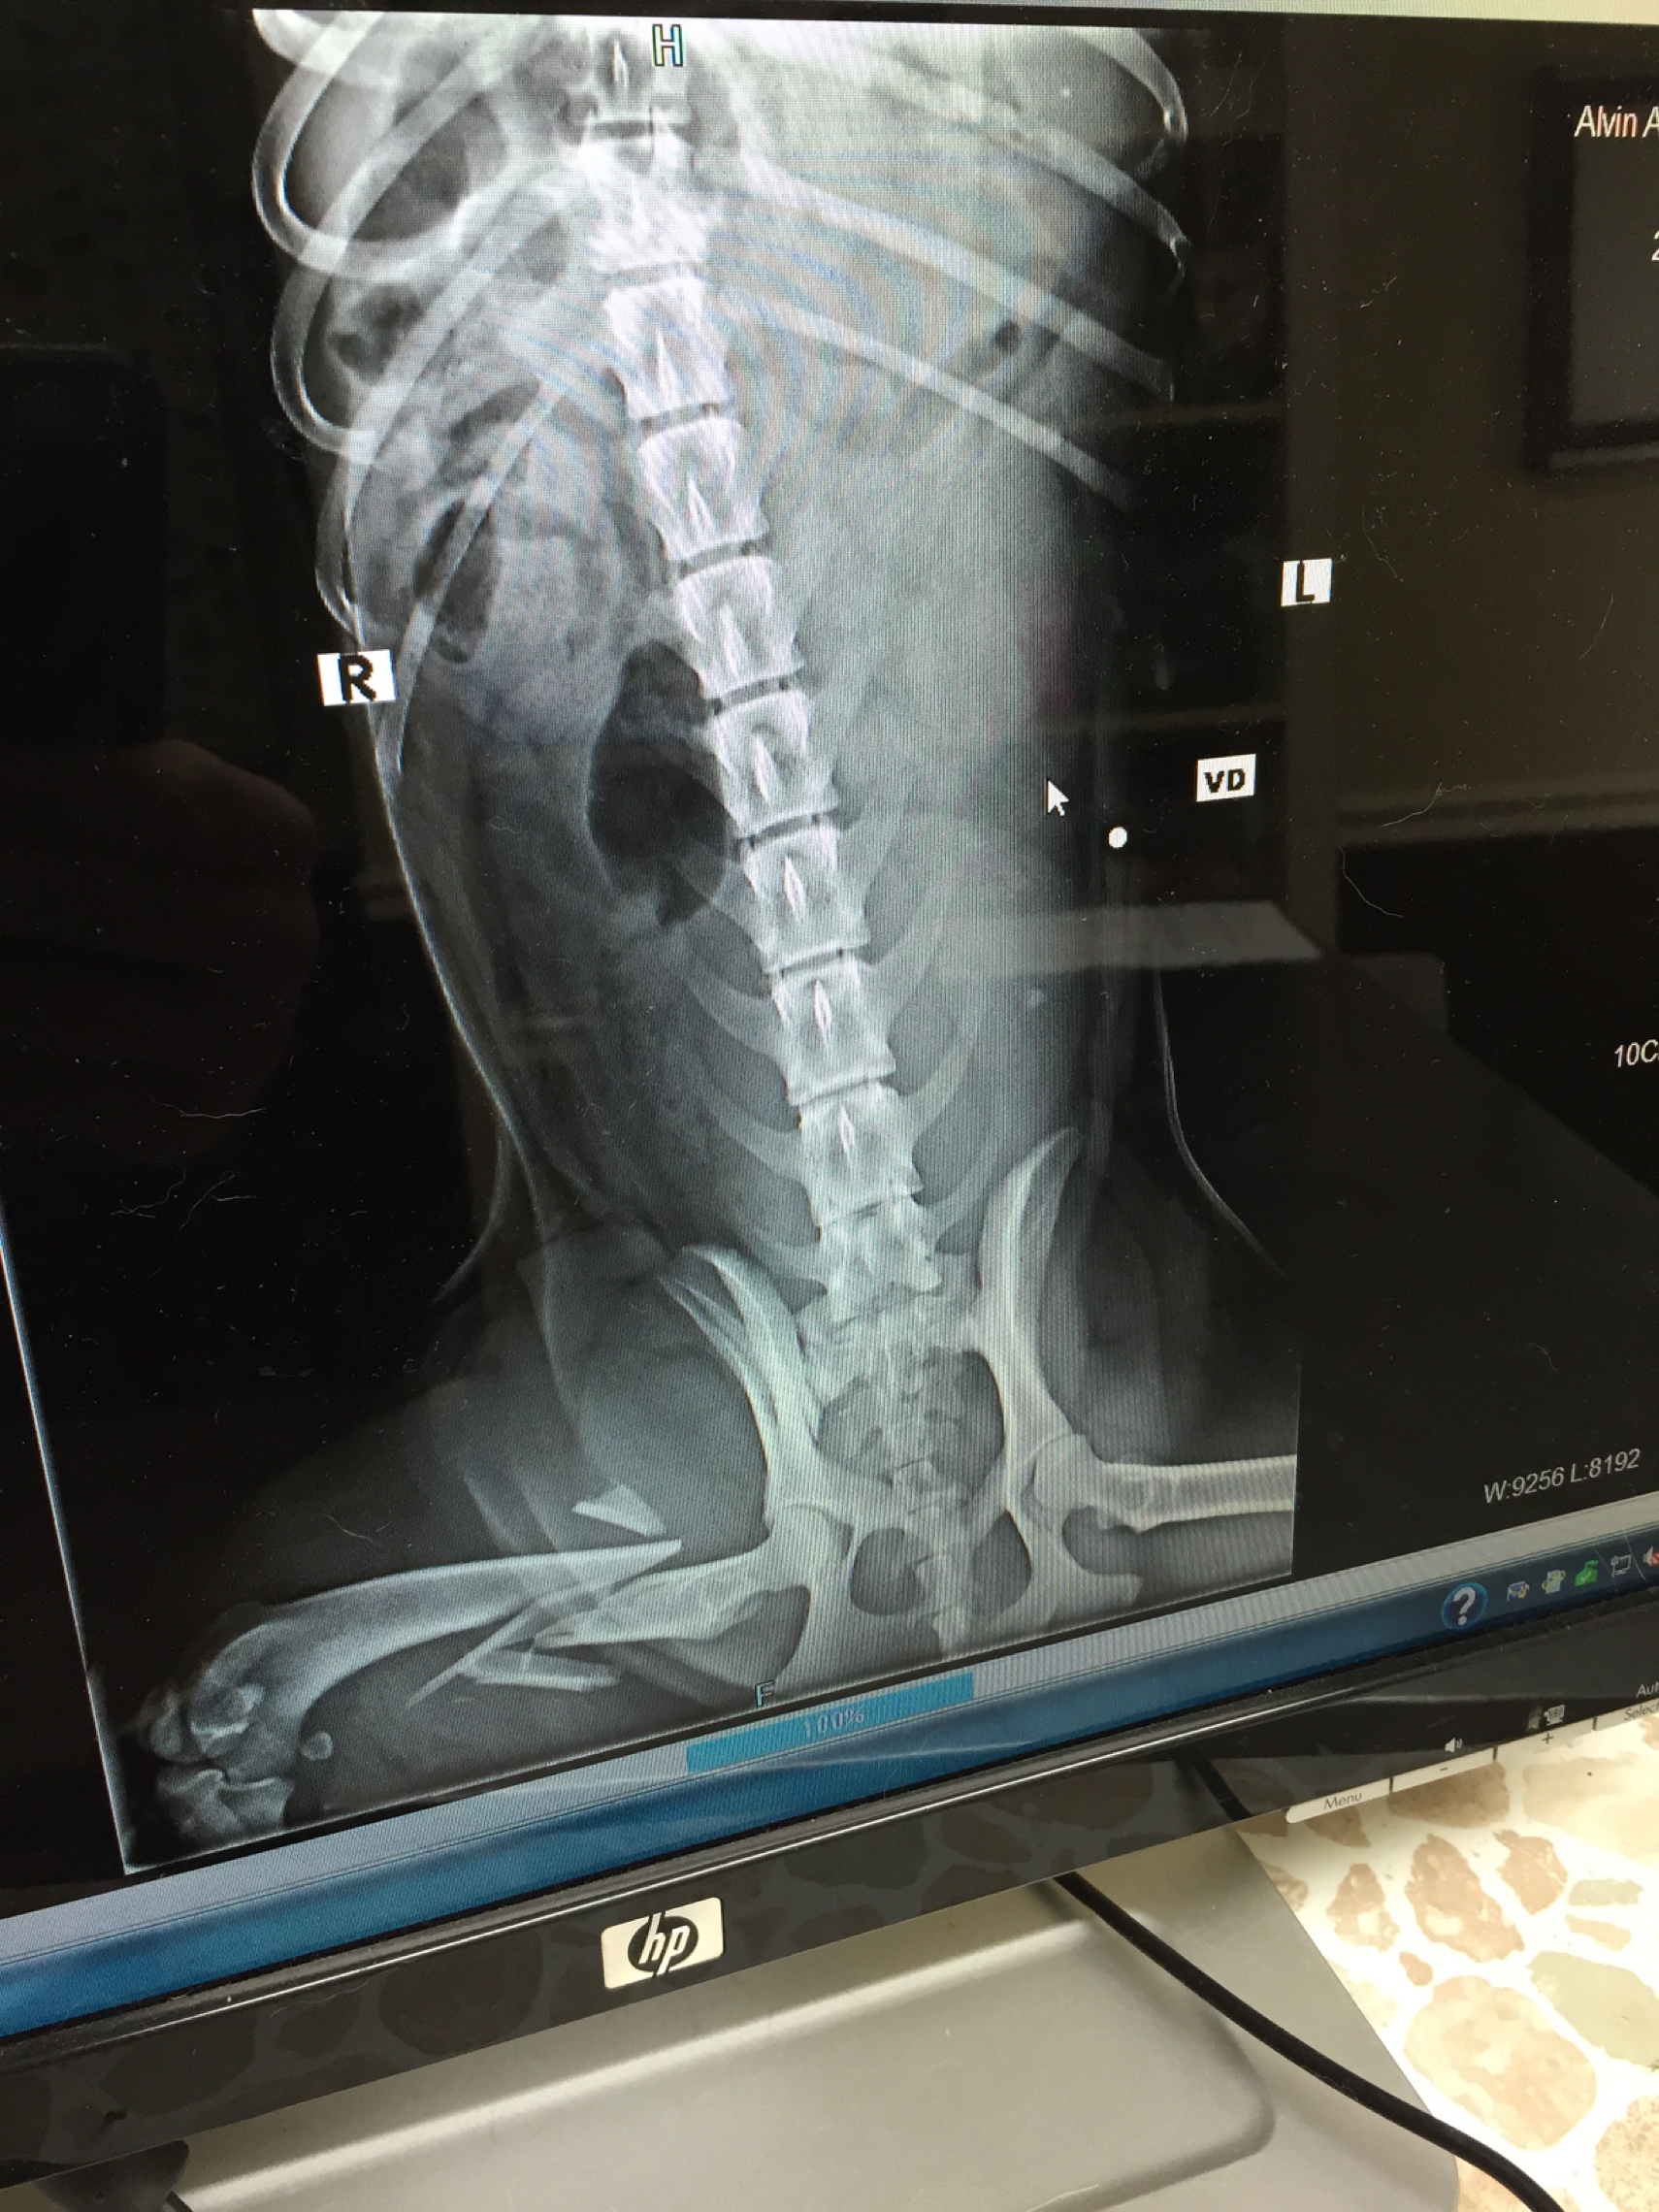

She has severve damage to her leg and back. The vet said he can save her but it will cost $10,000. She is not just a dog she is a companion, she is family. I need your help please for her and my family. I rescued her as a pup from abuse and I don't want her leaving this world that way.

She has severve damage to her leg and back. The vet said he can save her but it will cost $10,000. She is not just a dog she is a companion, she is family. I need your help please for her and my family. I rescued her as a pup from abuse and I don't want her leaving this world that way.